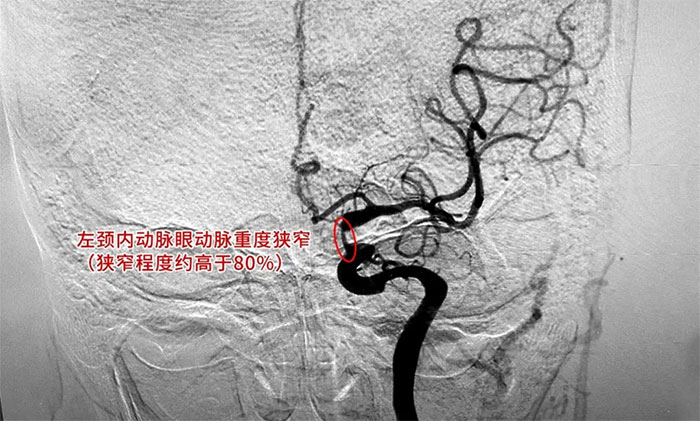

为进一步明确诊断并制定治疗方案,周君主任与医院学术副院长兼神经内科4A病区主任席刚明教授对患者病情开展了讨论评估,由席教授为患者进行DSA全脑血管造影检查,造影可见左颈内动脉岩骨水平段中度狭窄,左颈内动脉海绵窦段轻度狭窄,左颈内动脉眼动脉重度狭窄(狭窄程度约高于80%)。

▲ DSA检查影像

临床上,狭窄高于50%低于70%有明显症状,或狭窄高于70%,以及检查发现为不稳定斑块者,应通过手术治疗予以干预。在明确指征,排查手术禁忌,进一步完善手术预案并获得家属同意后,席刚明教授为患者进行了左颈内动脉球囊扩张+支架置入手术。术中,随着支架的顺利置入,造影可见左颈内动脉眼动脉段狭窄明显得到改善。

▲ 术后可见狭窄明显改善